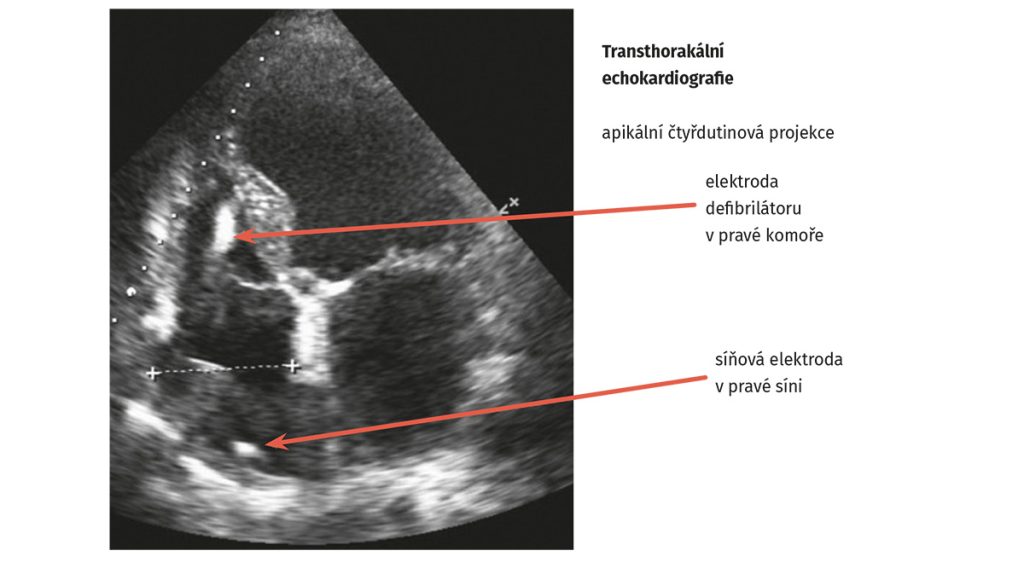

Byla doplněna nukleární magnetická rezonance srdce prokazující netransmurální ischemické ložisko v oblasti spodní a boční stěny levé komory se snížením ejekční frakce levé komory < 40 %. Vzhledem k těžké dysfunkci levé komory byla u pacienta provedena implantace defibrilátoru (ICD) v primární prevenci náhlé srdeční smrti (obr. 1 a obr. 2).

Obr. 2 Echokardiografie po implantaci defibrilátoru